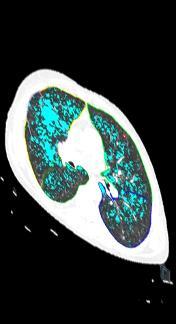

Lung cancer screening Chest CT Pulmonary lesions – Chest X-Ray